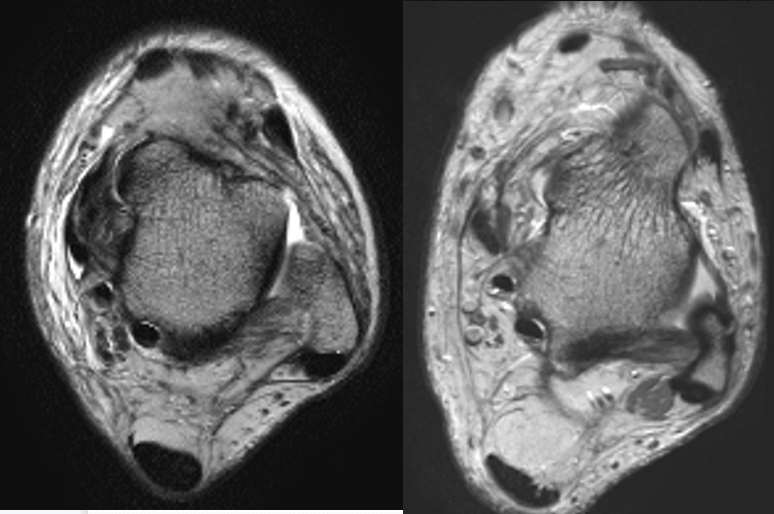

韧 带 显 示 技 术 要 点

T1WI及PDWI能清晰显示踝关节解剖,T2WI及脂肪抑制技术对显示病变有更大的帮助。横断面及冠状面能够显示大多数的韧带,应首先考虑行横断面和冠状面扫描,矢状面作为适当的补充

不同可疑韧带损伤的韧带选择最佳扫描层面:

①距腓前韧带:以20°斜断面效果最佳

②跟腓韧带:以-15°斜断面效果最佳

正常踝关节韧带MR表现

内、外侧韧带及肌腱在所有序列中均表现为条或带状低信号改变;

由于韧带间脂肪信号的镶嵌,韧带在MRI上常表现为纤维条索样改变;